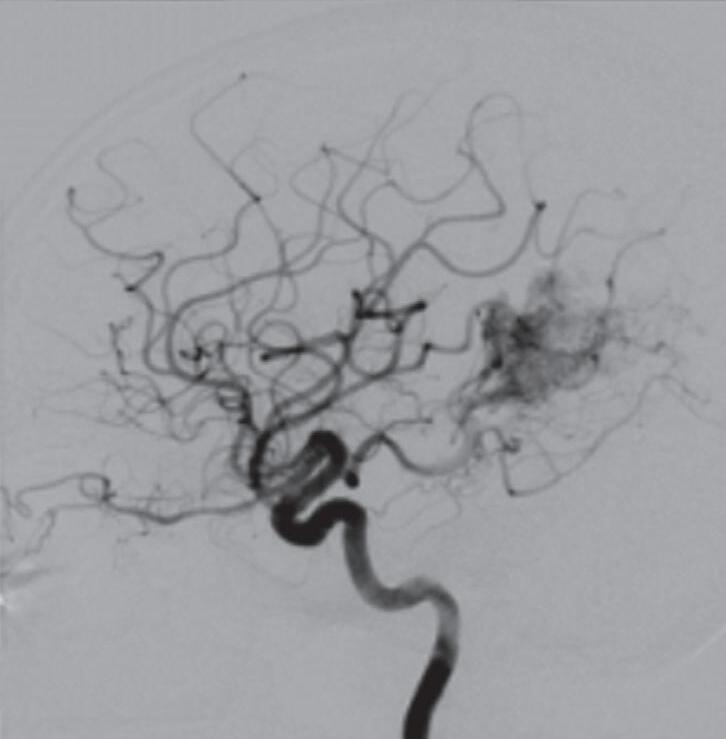

Fig. 1-8. (a-c) RNM T1 com contraste, cortes sagital (a), coronal (b) e axial (c) demonstrando MAV não rota com nidus localizado no lobo occipital à esquerda (setas longas). (d) Arteriografia digital cerebral com injeção de contraste via carótida direita (AP) mostrando a contribuição da carótida direita na irrigação da MAV contralateral. (e,f) Com injeção de contraste via carótida esquerda, em Perfil e AP respectivamente, observa-se nidus compacto nutrido por ramos da artéria cerebral média à esquerda e a veia de drenagem precoce se dirigindo para o seio sagital superior. Projeções em AP (g) e em perfil (h) demonstrando a contribuição do sistema vertebrobasilar por meio de ramos distais da artéria cerebral posterior à esquerda e drenagem para os seios sagital superior e sigmoide à esquerda (setas curtas).